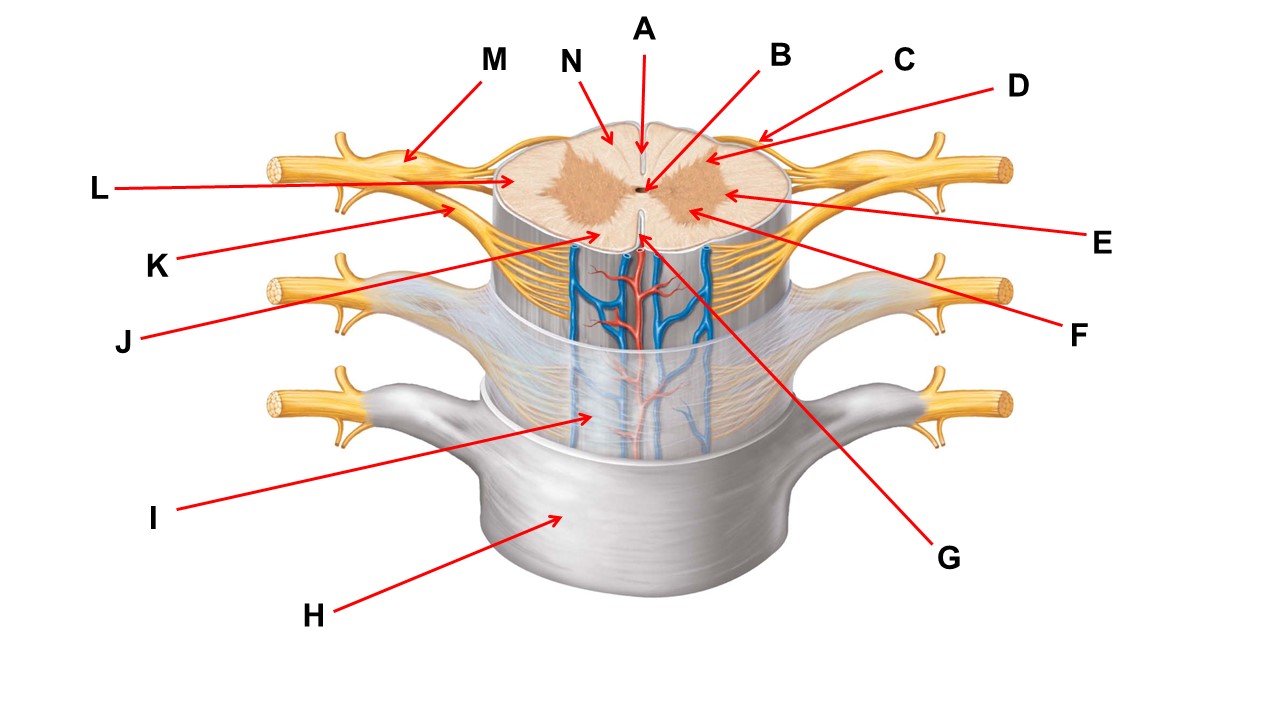

Name the region within bracket D.

Name the region of tissue surrounding the tip of arrow E.

Name the region of tissue surrounding the tip of arrow B.

Name the structure at the tip of arrow K.

ventral root

Name the region of tissue surrounding the tip of arrow J.

ventral column

Name the layer at the tip of arrow I.

arachnoid mater

Name the region of tissue surrounding the tip of arrow E.

lateral horn

Name the region of tissue surrounding the tip of arrow N.

dorsal column

Name the deep groove at the tip of arrow G.

anterior median fissure

Which structure(s ) would be found in the area at the tip of arrow D.

cell bodies of interneurons

Name the region of tissue surrounding the tip of arrow E.

ventral horn

Name the region within bracket G.

gray commisure